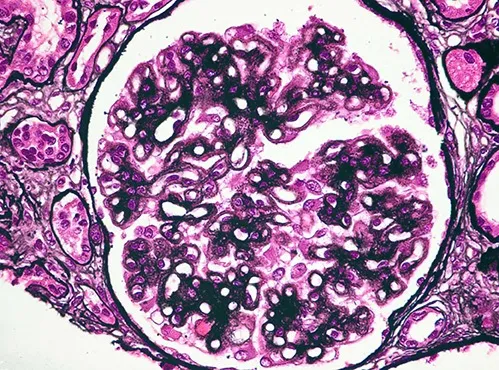

Desescalada de inmunosupresores en la Nefritis Lúpica

Desescalada de inmunosupresores en la Nefritis Lúpica